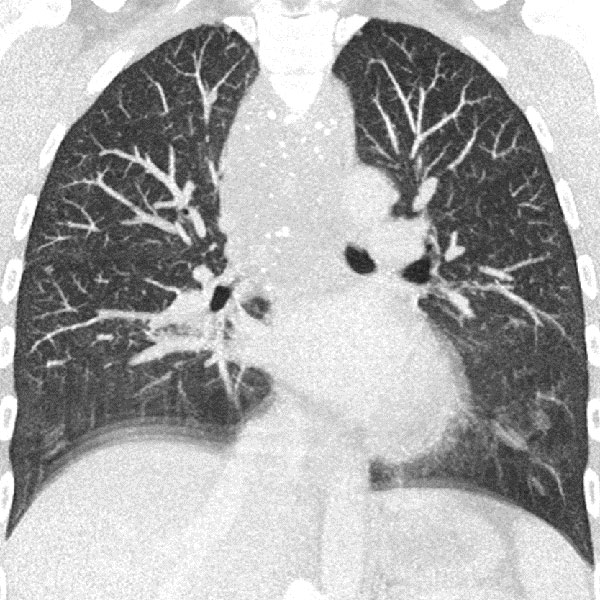

33-jährige Patientin, seit Kindheit immer wieder Anfälle von „Pseudokrupp“ mit ausgeprägtem respiratorischen Stridor. Vorbekanntes „Hämangiom“ unklarer Genese am Hals. In einer alten Thorax-CT ausgedehnte Raumforderung am Hals, Hypopharynx, Larynx bis ins Mediastinum. Gut sichtbar die multiplen Phlebolithen im Mediastinum, diese hinweisend auf eine venöse Malformation.